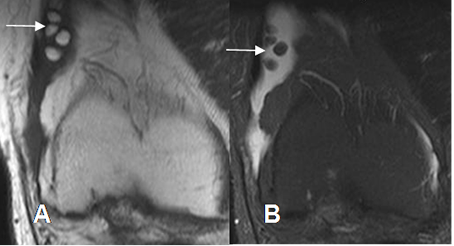

Fig 72. Condromatosis sinovial.

A: RM coronal en T1 y B: RM coronal en STIR. Cuerpos libres no calcificados, con SI similar a la medula ósea.

Fig 73. Condromatosis sinovial.

A: RM axial en T2 y B: RM sagital en T2. Cuerpo libre moderadamente calcificado, en el interior de un quiste de baker.